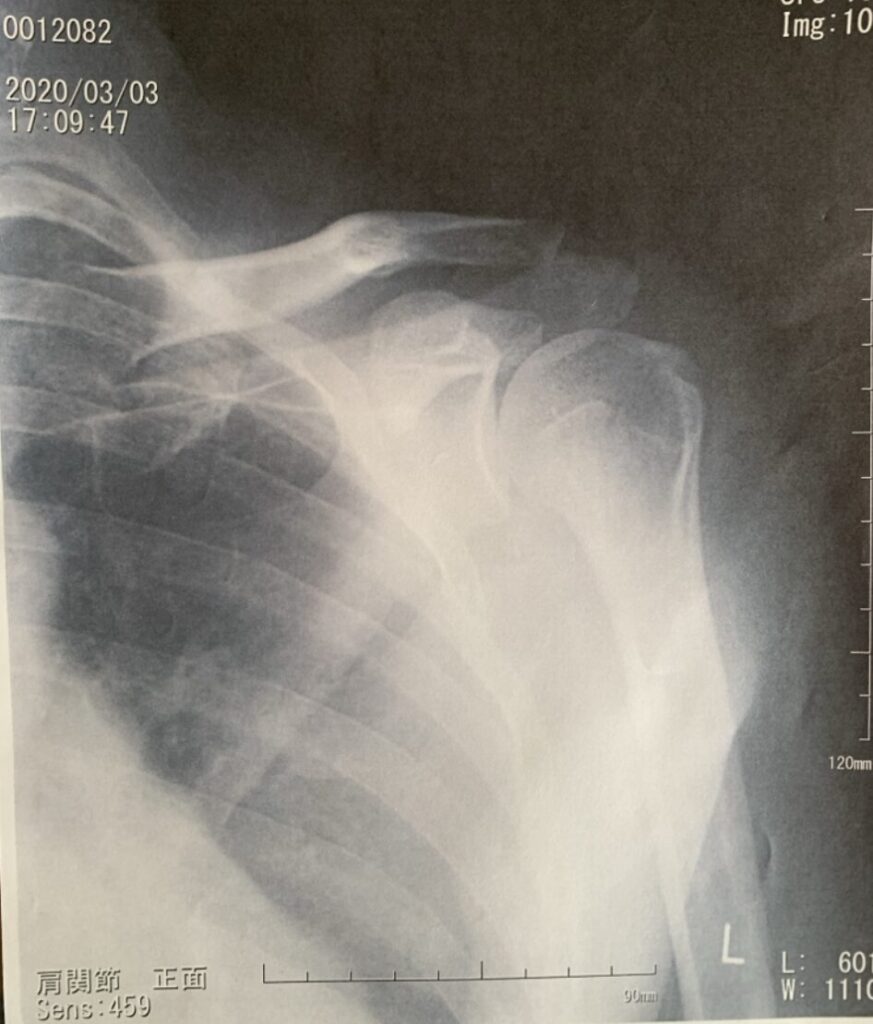

結果は悲惨でした。「左肩腱板断裂」という重傷を負い、2週間の入院と2年間のリハビリを余儀なくされました。

(※腱板断裂:肩の関節を安定させる筋肉が切れ、激しい痛みで腕が上がらなくなる怪我)

A. 諦める必要はありませんが、「リハビリの科学」を取り入れてください。 私は腱板断裂から復帰しましたが、その過程で「どの筋肉を動かせば痛くないか」を徹底的に学びました。怪我は自分の体を知るチャンスでもあります。